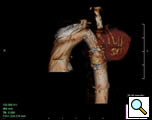

At our institution a dedicated CT angiogram of the chest was obtained to better define the morphology of the patient’s arch and aneurysm. This confirmed the finding of a saccular aneurysm just distal to the left subclavian artery takeoff. Because of the patient’s prior history of coarctation recurrence and repair, this was felt most likely to represent a pseudoaneurysm, possibly at the site of a patch repair. Aortic reconstructions of the CT angiogram showed no evidence for recurrence of the coarctation (Figure 2). There was, however, a size discrepancy in the diameter of the aorta above and below the aneurysm. The diameter of the aortic arch between the left carotid and left subclavian arteries was 13mm. The diameter of the descending thoracic aorta distal to the aneurysm was 23mm.